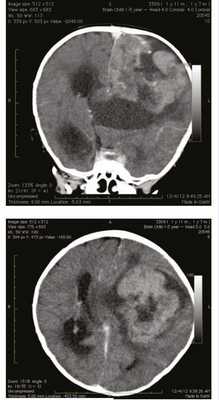

Мальчик в возрасте 1 года 10 мес поступил во II детское отделение ФГБУ «Научно-исследовательский институт нейрохирургии им. акад. Н.Н. Бурденко» с гигантской опухолью левого полушария головного мозга. Ребенок от первой беременности, протекавшей без патологии, первых самостоятельных родов на 37-й неделе. Масса тела при рождении 2750 г, рост 49 см. Мальчик развивался с отставанием в моторном развитии: начал переворачиваться в 6 мес, ползать и сидеть в 7 мес, ходить в 1 год 1 мес. Заболел в возрасте 1 года 7 мес, когда на фоне подъема температуры до 38 °С стал прихрамывать на правую ногу. Проведенная компьютерная томография (рис. 1)

Рисунок 1. Компьютерная томография гигантской опухоли левого полушария головного мозга. выявила гигантскую опухоль левого полушария головного мозга. Также за прошедшие 3 мес отмечен активный прирост окружности головы. В клинической картине заболевания доминировали симптомы внутричерепной гипертензии в виде прогрессирующей макрокрании (окружность головы 60 см), на глазном дне были выявлены признаки внутричерепной гипертензии с развитием атрофии зрительных нервов и слепоты. Также обращала на себя внимание очаговая симптоматика преимущественного поражения левого полушария: ограничение взора влево, центральный парез VII нерва справа, тетрапарез до 4 баллов слева и до 3 баллов справа, рефлексы D>S, диссоциация по оси тела и координаторные расстройства с развитием выраженной атаксии, при этом движения в конечностях были сохранены в полном объеме. Мальчику было проведено тотальное удаление гигантской опухоли, имеющей достаточно хорошую псевдограницу с веществом мозга. После гистологической верификации опухоли ребенок и его родители были консультированы онкологом: было рекомендовано проведение высокодозной химиотерапии. Через 3 мес после постановки диагноза ребенок умер от прогрессии заболевания.

За исключением небольших замороженных во время операции фрагментов опухоли был исследован весь присланный материал, составивший 12 парафиновых блоков. Гистологическое исследование показало достаточно однородную по морфологической картине злокачественную опухоль с обширными полями некрозов. Клетки опухоли формировали нейроэпителиальные структуры: каналы, полости и трабекулы, подобные нервной трубке эмбриона. Также в опухоли встречалось большое количество истинных многорядных розеток с фигурами митозов

Рисунок 2. Медуллоэпителиома. Гистологические препараты. а — общий вид опухоли, формирующей эпителиальные структуры (голубые стрелки) и истинные розетки (желтая стрелка). × 10; б — структуры, подобные нервной трубке (красные стрелки), и истинные розетки (голубая стрелка). × 30. Окраска гематоксилином и эозином. Участки нейропиля в опухоли отсутствовали. Иммуногистохимическое исследование выявило положительную экспрессию LIN28А (рис. 3), Рисунок 3. Медуллоэпителиома. Иммуногистохимическое исследование с антителом LIN28A. Тотальная положительная экспрессия в клетках опухоли. виментина, очаговую положительную экспрессию цитокератинов АЕ1/3 и СК18 (рис. 4); Рисунок 4. Медуллоэпителиома. Иммуногистохимическое исследование с эпителиальным маркером цитокератином СК18. Фокальная положительная экспрессия в клетках опухоли. тотальную ядерную экспрессию INI1, что свидетельствовало об отсутствии делеции гена INI1 и исключило атипическую тератоидно-рабдоидную опухоль. Экспрессии глиофибриллярного кислого белка GFAP, S-100, синаптофизина, нейронспецифической енолазы NSE, эпителиального мембранного антигена EMA и альфа-фетопротеина выявлено не было. Флуоресцентная гибридизация in situ демонстрировала кластерную амплификацию микро-РНК локуса 19q13 (рис. 5), Рисунок 5. Флуоресцентная гибридизация in situ с некоммерческой двухцветной пробой. FITC-меченной пробой 634C1 к локусу 19q13.42 и контрольной дигоксигенинмеченной пробой 2659N к локусу 19р13 выявлена кластерная амплификация микро-РНК локуса 19q13.42 (множественные сливные зеленые сигналы). Вверху в центре имеется канал (зеленые стрелки) структура, подобная примитивному эпителию развивающегося мозга; внизу слева (красная стрелка) — истинная многорядная розетка. количественных изменений на хромосоме 2 не наблюдалось (сбалансированный профиль хромосомы 2) (рис. 6). Рисунок 6. Флуоресцентная гибридизация in situ с пробой Vysis к онкогену N-MYC (локус 2p24)/центромера 2 не выявила добавки хромосомы 2. В центре — истинная многорядная розетка (показано стрелкой).